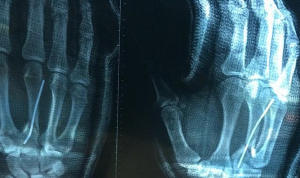

« La vague m’a emporté et m’a balancé direct sur le récif, j’ai atterri sur la main et l’arrière de ma tête a tapé le récif. Je me suis cassé la main ainsi qu’une vertèbre. J’ai toujours mal. »